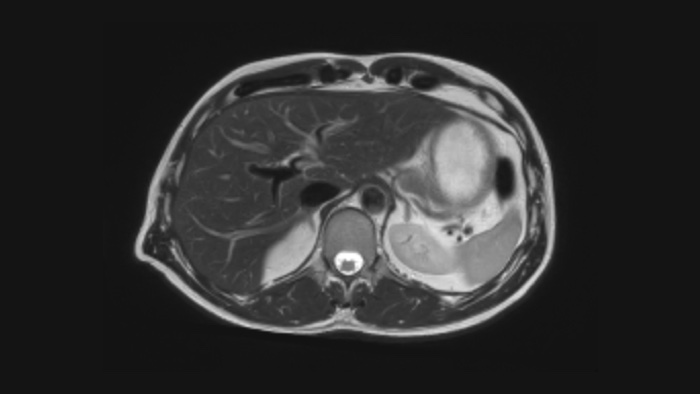

Diagnostic confidence Expand your imaging capabilities in all clinical areas. See how your peers are benefiting.

The Ingenia Ambition 1.5 Tesla magnet is the next generation of MR technology. It brings together the most important aspects of having a successful MR system.

This innovative solution offers many clinical, operational and financial benefits.